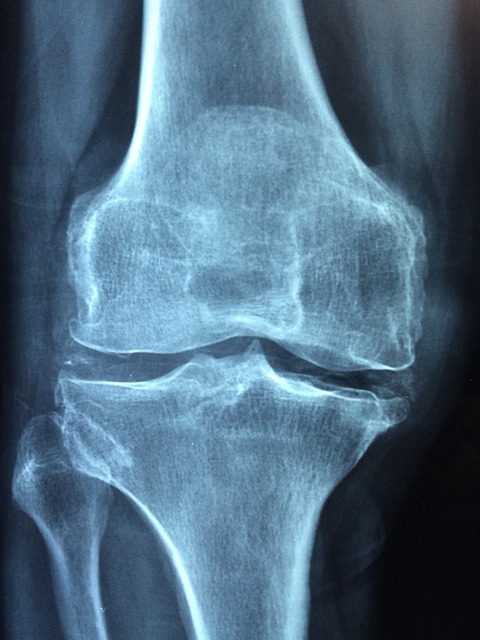

골다공증은 뼈가 약해지고 쉽게 부러질 수 있는 상태로, 주로 뼈의 질량 감소와 구조적 변화에 의해 발생합니다. 이는 노화 과정에서 자연스럽게 나타날 수 있지만, 특정 조건이나 생활습관에 의해 악화될 수 있습니다. 특히 폐경 후 여성은 에스트로겐 수치 감소로 인해 골다공증 위험이 높아집니다. 또한, 가족력, 낮은 체중, 흡연, 과도한 음주, 신체 활동 부족 등이 주요 원인으로 작용합니다.